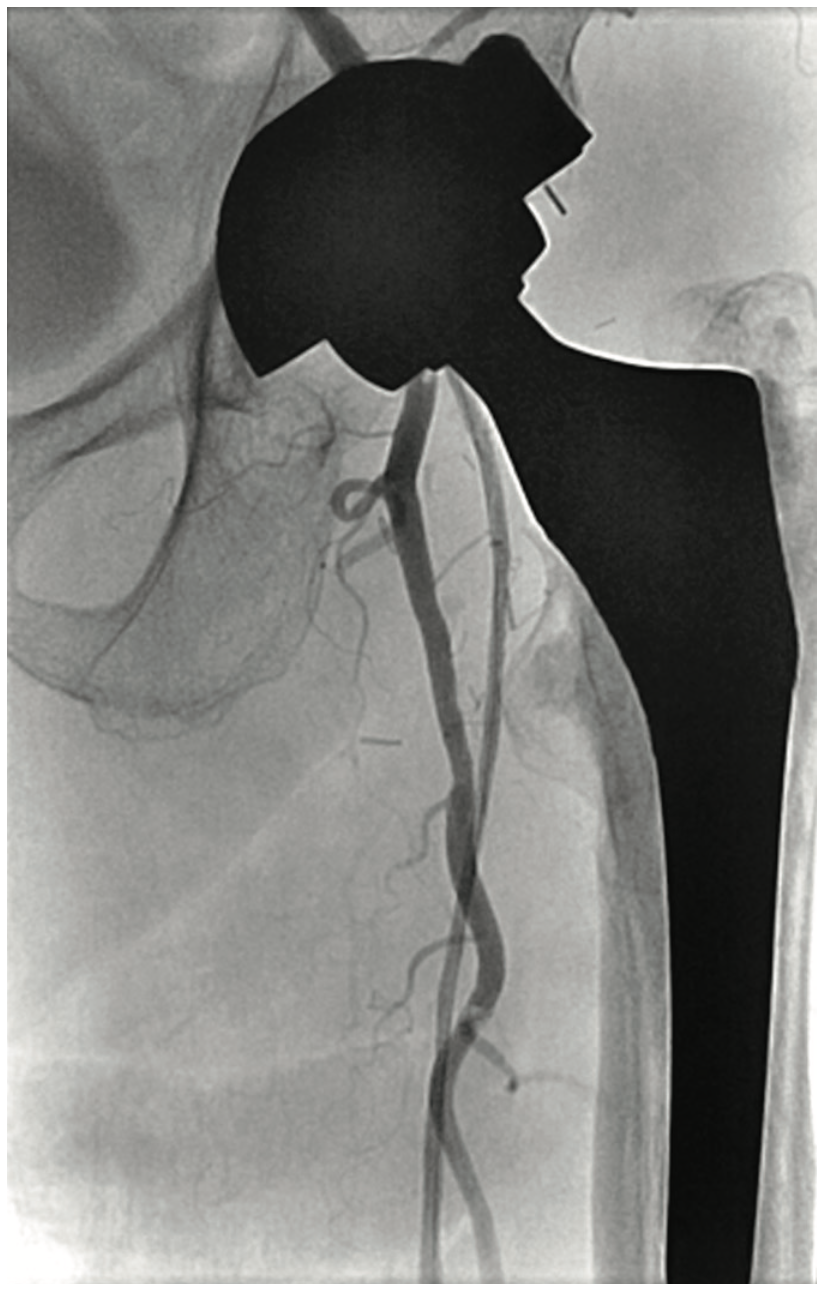

A 63-year-old male smoker presented with critical limb ischemia of his left foot. Four years prior, the patient underwent right fem-pop bypass after failed intervention on his right leg. He ended up losing the fifth digit on his right foot. Three years prior to his visit, he underwent a fem-pop bypass procedure on his left leg for severe claudication after failed intervention. One year later, he underwent a redo fem-pop on his left leg with a cadaveric vein. Twelve months prior to the visit, a self-expanding stent was placed in that fem-pop graft because of continued foot ischemia. Seven months prior to his visit, his symptoms re-occurred, and the patient was told nothing could be done after an angiogram showed the vessel was occluded. The patient suffered from polyneuropathy and was unable to walk, but did not want amputation. The patient was on cilastazol and coumadin, and had type II diabetes mellitus. His exam revealed a cool and red left foot, but no ulcers. Capillary filling was adequate. The right dorsalis pedis was normal, and there was no popliteal pulse on either side and no left pedal pulses. A contralateral approach was utilized and revealed the graft was occluded on the left side (Figure 1). The patient likely had thrombus in the graft, and we felt that a laser would be appropriate, used either in the traditional manner or with the step-by-step method. Whenever the step-by-step method is utilized, we use the CrossLock LP device (Radius Medical) for centering (Figure 2). The CrossLock LP is usually utilized for infrapopliteal lesions, but in this case, the 3 mm elastomeric balloon would fit well into the nub of the bypass graft. We immediately subtended the bypass graft all the way down and then were able to access the infrapopliteal vessels (Figures 3-4). We performed .9 mm laser (Spectranetics) in the graft and balloon angioplasty (Figure 5). Two Xience stents (Abbott Vascular) were placed, a 4.0 cm and 3.5 cm, at the anastomosis site, and because of residual stenosis at the popliteal, we placed a 5.5 cm Supera stent (Abbott Vascular). Due to multiple failures of the graft, the graft was covered with a 6.0 mm x 250 mm Gore Viabahn stent graft (W.L. Gore & Associates). At the end of the procedure, we were able to achieve brisk 2-vessel runoff (Figures 6-7). Fluoroscopic time was long at 73 minutes and the contrast utilization was 236 mL.